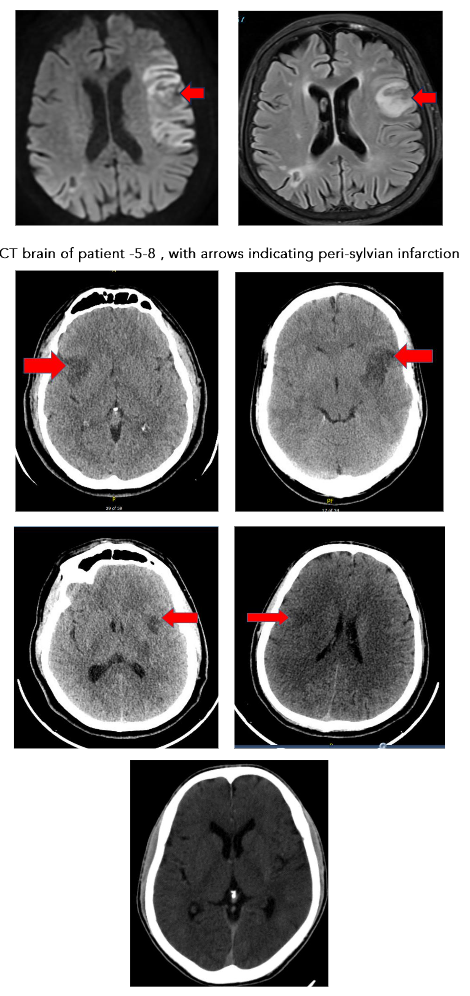

Aphasia was the most common clinical presentation, appearing in seven out of ten cases, with accompanying hemiparesis noted in four patients. Nine of the ten patients with primary APS experienced strokes in the M2 segment of the middle cerebral artery, predominantly resulting in peri-sylvian infarcts.

With a notable prevalence in the left peri-sylvian region (6 out of nine patients). Only one patient presented with a posterior circulation stroke, exhibiting a top of basilar syndrome. CT angiography revealed a left M2 occlusion in one case and distal basilar occlusion in another, while the remaining cases had no significant angiographic findings. 2D Echo was normal in all patients. TEE was done in 3 patients, which was normal. Holter study was normal in all patients.

The clinical and radiological profile of ischemic strokes associated with APS, as observed in this case series, reveals distinctive patterns in symptomatology and imaging that reinforce previous studies yet also highlight unique characteristics. The predominance of peri-sylvian infarcts in the M2/M3 segments of the middle cerebral artery, especially affecting the left hemisphere, aligns with findings that cortical strokes with aphasia as the primary presentation are often linked to embolic strokes. Studies have similarly observed that ischemic events in APS patients tend to exhibit neuroimaging patterns indicative of embolic mechanisms, often resembling cardioembolic stroke distributions. This correlation emphasizes the role of APS as a prothrombotic condition with implications for early detection and management of stroke in young patients, regardless of traditional vascular risk factors.

Recent studies emphasize the importance of specific MRI findings in diagnosing APS-related CNS involvement. Graf (2017) underscores the role of MRI in detecting small, scattered ischemic lesions, often located in cortical and subcortical regions, which are indicative of embolic phenomena. These findings align with the peri-sylvian infarct patterns noted in this case series.

Advanced imaging techniques, such as diffusion-weighted imaging (DWI), provide additional diagnostic value. DWI often reveals acute ischemic lesions in multiple vascular territories, which are characteristic of APS-related strokes and highlight the embolic origin associated with aPLs.